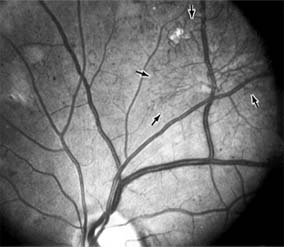

BRANCH RETINAL VEIN OCCLUSION

Branch retinal vein occlusion presents as sudden unilateral vision loss with segmentally distributed intraretinal hemorrhage. The vein occlusion always occurs at the site of an arteriovenous crossing (Figure 10-29), and retinal neovascularization may develop if the occlusion produces an area of retinal capillary nonperfusion that is more than 5 disk diameters in area. Sight-threatening complications of the disease are macular edema, macular ischemia, and vitreous hemorrhage from retinal neovascularization.

Figure 10-29

Figure 10-29: Branch retinal vein occlusion involves the superotemporal vein. The point of obstruction (arrow) is at an arteriovenous crossing.